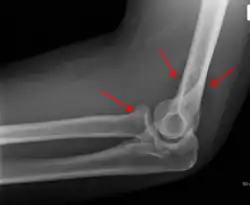

The fat pad sign, also known as the sail sign, is a potential finding on elbow radiography which suggests a fracture of one or more bones at the elbow. It may indicate an occult fracture that is not directly visible. Its name derives from the fact that it has the shape of a spinnaker (sail).[1] It is caused by displacement of the fat pad around the elbow joint. Both anterior and posterior fat pad signs exist, and both can be found on the same X-ray.

In children, a posterior fat pad sign suggests a condylar fracture of the humerus. In adults it suggests a radial head fracture.

The fat pad sign is invaluable in assessing for the presence of an intra-articular fracture of the elbow. An anterior fat pad is often normal. However a posterior fat pad seen on a lateral x-ray of the elbow is always abnormal. The patient will be unable to flex their elbow and requires orthopaedic input.[2]

The posterior fat pad is normally pressed in the olecranon fossa by the triceps tendon, and hence invisible on lateral radiograph of the elbow.[3] When there is a fracture of the distal humerus, or other pathology involving the elbow joint, inflammation develops around the synovial membrane forcing the fat pad out of its normal physiologic resting place. This is visible as the "posterior fat pad sign" and is often the only visible marker of a fracture, particularly in the pediatrics population.